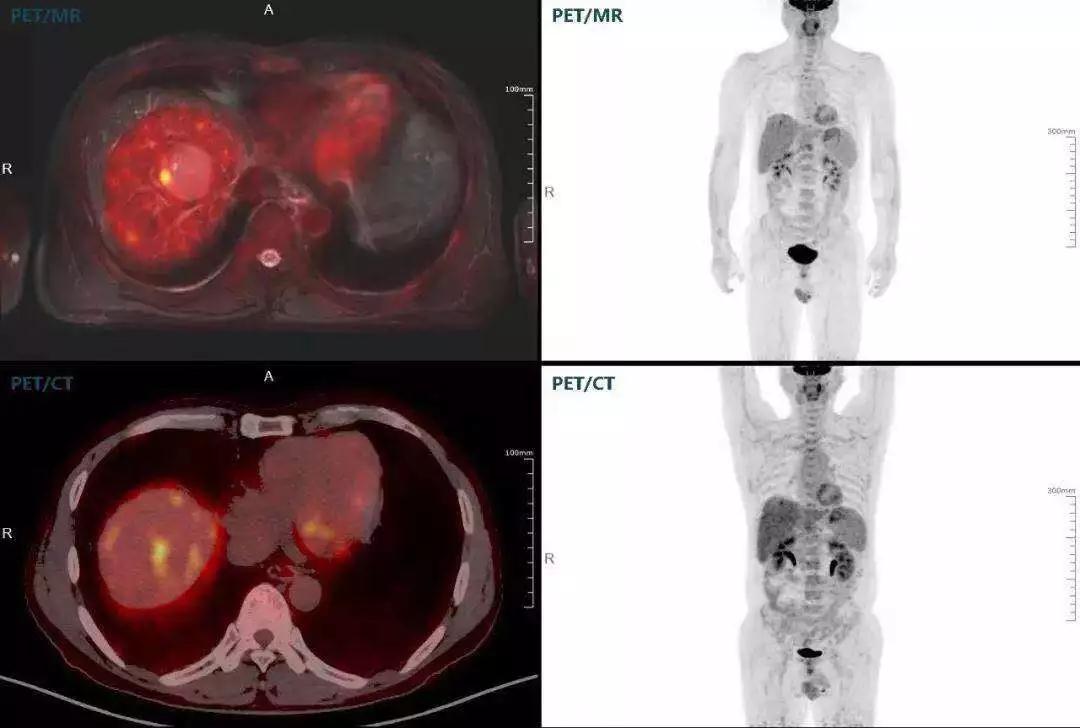

(對(duì)于同一例肝臟惡性腫瘤,PET-CT與PET/MR成像對(duì)比。可以看到,聯(lián)影PET/MR圖像對(duì)腫瘤邊界和FDG高濃聚區(qū)域清晰顯示。)